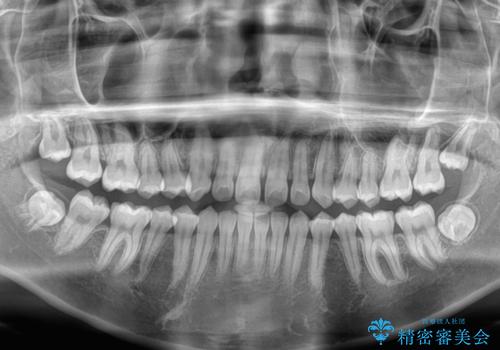

- 前歯の隙間を気にして来院された患者様です。

口元の突出感があり、小臼歯4本を抜歯して口元を引っ込める矯正治療も提案しましたが、本人は口元の突出感は気になっていないとのことで、インビザラインにて隙間やデコボコを改善することとしました。

軽度の歯列不正であったため、廉価版のインビザライン・モデレートパッケージにて治療を終えることができました。